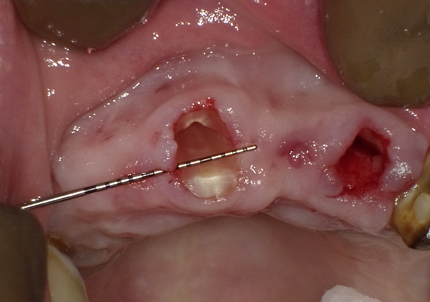

4.右上2番 S.S.T(ソケットシールドテクニック)

5.左上1番 S.S.T(ソケットシールドテクニック)

6.左上2番 S.S.T(ソケットシールドテクニック)